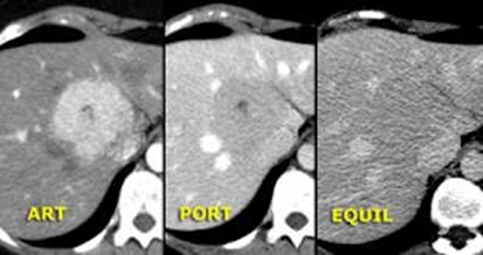

- Diaqnozu dəqiqləşdirmək üçün Qc venaları yoxlanılmalıdır. Bunun üçün dopler USM, KT-angioqrafiya, MRT-angioqrafiyalar və ya kontrastlı venoqrafiya edilir.

- Görüntüləmədə Qc venalarının trombotik tutulması diaqnozu dəqiqləşdirən əlamətdir.

Qaraciyər venalarının görünməməsi, kontrastlaşmaması və ya trombla tıxanması.

- Görüntüləmədə qaraciyər venalarının tıxanması, I seqment hipertrofiyası ola bilər (xroniki forma);